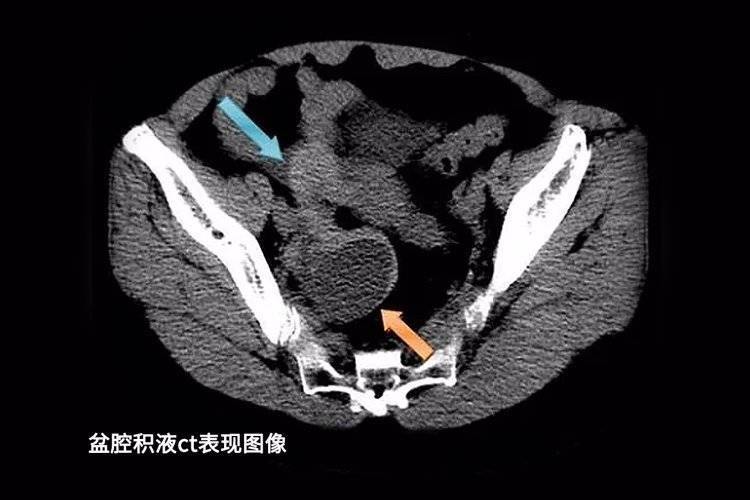

02、盆腔积液

我们的盆腔和腹腔内的各脏器本身就会分泌液体,液体的作用是润滑、保护盆腔器官和组织。检查单上的盆腔积液仅仅只是一种表现,并非疾病。

几乎所有的女性都会查出不同程度的盆腔积液,一般在3cm以下且身体没有其他不适,则无需特殊的处理。女性在排卵期、月经期或是月经刚结束时检查,积液可能会略微增加,这是正常的生理现象。